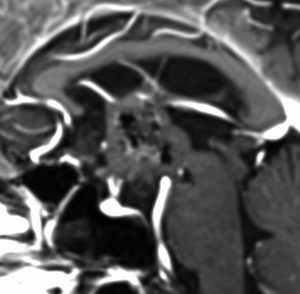

1968年 18歳の時に頭痛嘔吐で発症しました。第3脳室腫瘍と閉塞性水頭症の診断だけで,シャント手術を受けました。手術も化学療法も放射線治療もされていません。下の画像は60代で撮影されたものです。この例では,第3脳室内に増大した大きな毛様細胞性星細胞腫が,視床下部下垂体障害を出すことなく,自然経過で増大停止 growth arrest して,カチカチに固まってしまうということを教えてくれます。でも,こんなに都合よく経過観察できる例も珍しいです。

CTでは強い石灰化があります。右のT2強調画像では腫瘍は等信号,視交叉の後ろにあります。内部の低信号は石灰化です。

T1強調画像では等信号,ガドリニウム増強でごく一部がまだらに増強されます。